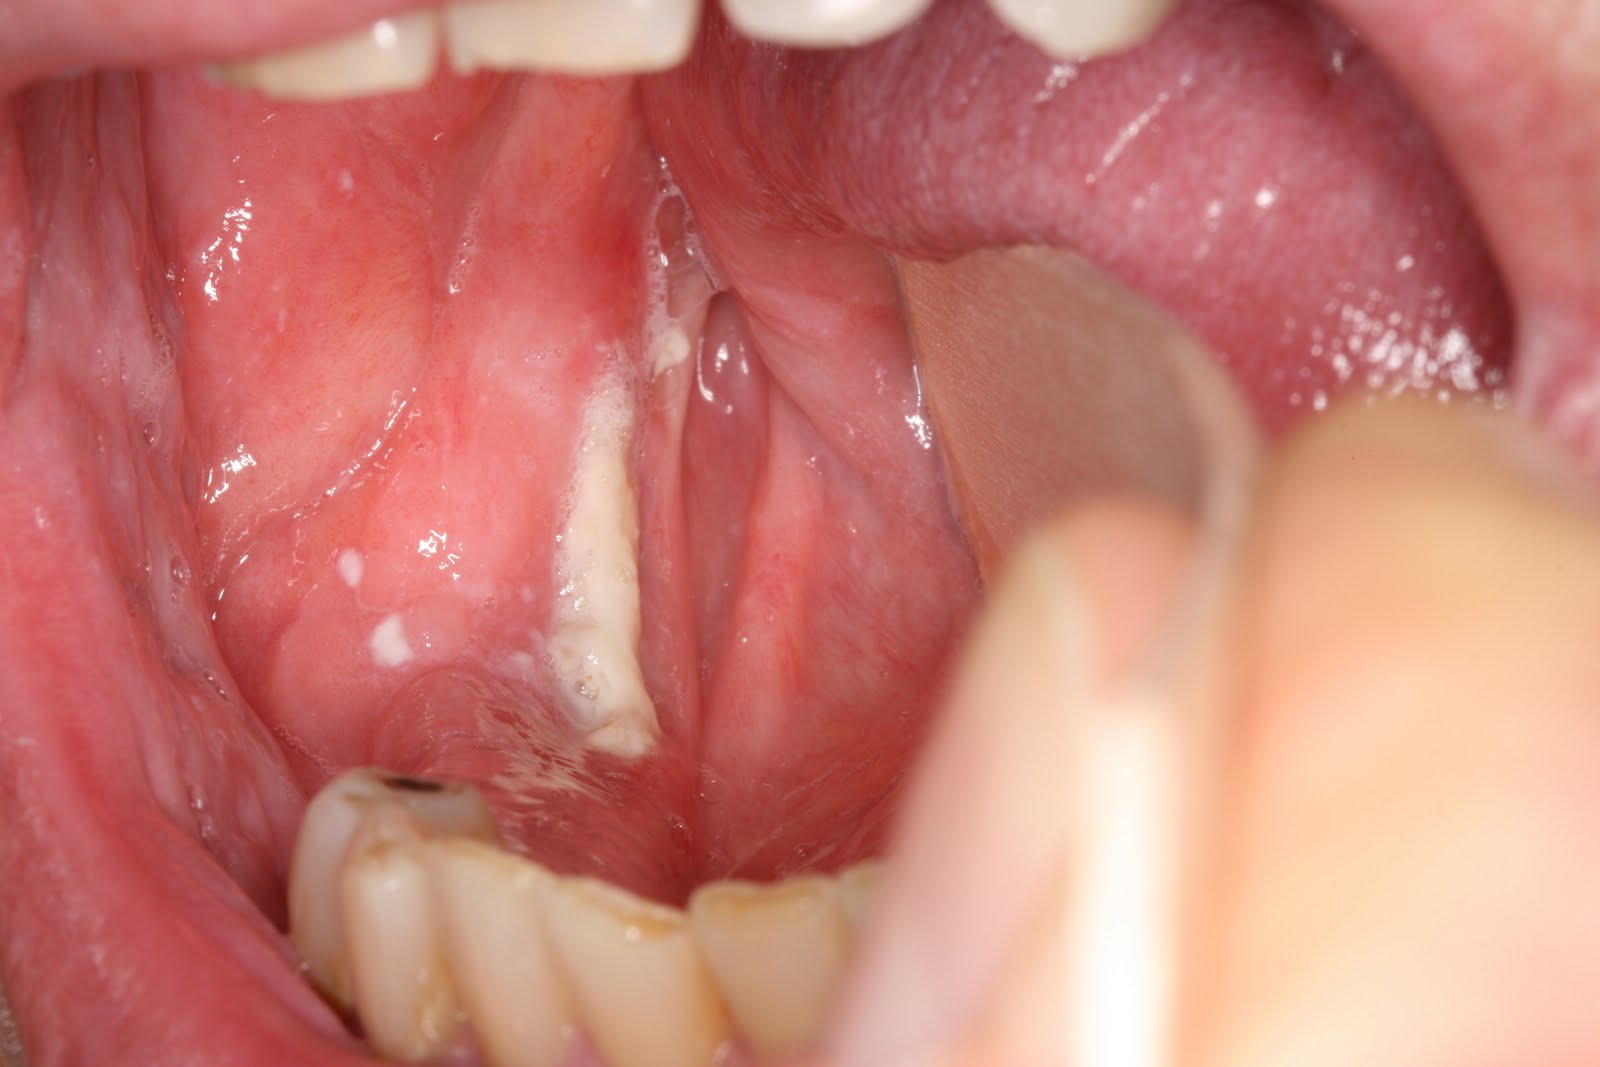

Τα στόμια των εκφορητικών πόρων των μεγάλων σιαλογόνων αδένων – ιδιαίτερα του υπογναθίου – που διοχετεύουν το σάλιο στο στόμα μπορούν επίσης να γίνουν αντικείμενα τραυματισμού (Εικόνα 9).

Εικόνα 9. α. Τραυματισμός στο στόμιο του εκφορητικού πόρου του αριστερού υπογναθίου αδένα (βέλος), β. Καθετηριασμός στο τραυματισμένο στόμιο του εκφορητικού πόρου της δεξιάς παρωτίδας (βέλος).